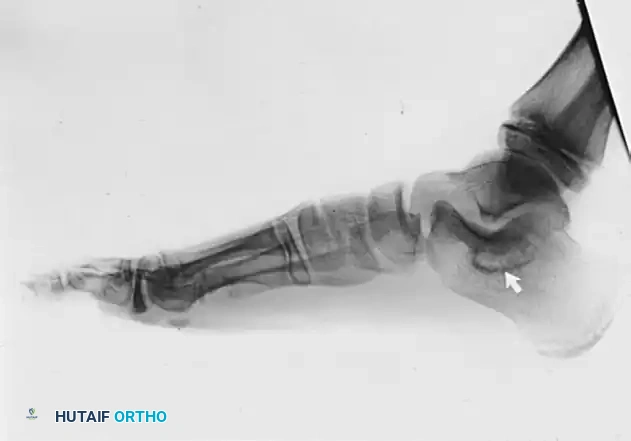

Advanced imaging is mandatory for surgical planning. While standard weight-bearing radiographs may demonstrate secondary signs such as talar beaking or the "C-sign" (a continuous C-shaped line formed by the medial outline of the talar dome and the inferior outline of the sustentaculum tali), Computed Tomography (CT) is the gold standard for defining the exact size, location, and osseous nature of the coalition.

FIGURE 82-84 A: Lateral radiograph of an immature foot demonstrating a middle facet tarsal coalition. Note the subtle obscuration of the subtalar joint space.

FIGURE 82-84 B: Lateral radiograph of a patient in their late 20s showing adaptive changes in the middle facet, including dorsal talar beaking secondary to altered midtarsal kinematics.

FIGURE 82-84 C: Harris axial calcaneal view, traditionally used to visualize the middle and posterior facets, demonstrating an abnormal medial joint space.

FIGURE 82-84 D: Coronal CT scan confirming degenerative changes in the middle and posterior facets. Note the adaptive changes of the entire shape of the calcaneus and the bridging bone at the sustentaculum tali.

FIGURE 82-84 E: Oblique radiograph of the same foot as in B and D, showing the coalition extending distal to the middle facet.